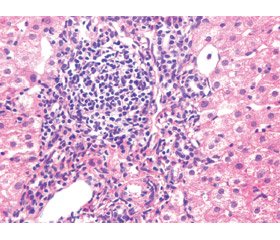

Для демонстрации эффекта ИФТ приводим примеры конкретных наблюдений (рис. 1–4).

/51/51.jpg)

/52/52.jpg)

/53/53.jpg)